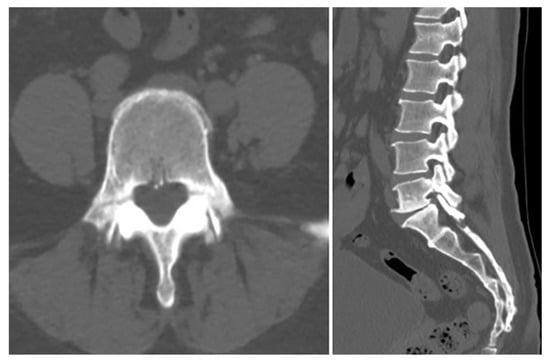

Further imaging evaluation was performed to confirm the previously diagnosed L5 bilateral pedicle fracture and to assess the involvement of surrounding structures. Figure 1A shows a plain radiograph taken during the initial examination in our hospital, revealing a subtly visible fracture at the pedicle of L5 and suspicious Meyerding grade 1 spondylolisthesis at the L5-S1 vertebrae. As shown in Figure 1B, dynamic flexion-extension lateral radiographs were performed to assess instability that could affect the treatment approach, and no abnormal findings were observed. Figure 1C shows a CT scan confirming isolated bilateral pedicle fractures at L5, consistent with the findings from the previous examination at the local clinic, and no additional fractures were identified. There were no sclerotic changes surrounding the fracture lines or pseudoarthrosis, suggesting an acute fracture despite the absence of recent trauma history. Pars defects or hypoplastic neural arch were not observed. Figure 2 shows MRI findings demonstrating low signal intensity on T1 and T2 weighted images in the bilateral pedicle lesions, consistent with acute lesions, and minimal hyperintense marrow edema surrounding the fracture lines on T2. Additionally, imaging revealed mild degenerative changes, including disc bulging at L3–4, L4–5, and L5–S1, and Modic type 2 at L5–S1. These disc lesions showed no features suggestive of an acute rupture and were more compatible with chronic degenerative changes rather than acute pathology. Given the absence of pre-existing LBP or neurologic symptoms, these degenerative findings were regarded as incidental and unrelated to the patient’s current presentation.

Figure 2. MRI showing low signal intensity on T1- and T2-weighted images in the bilateral L5 pedicles with minimal hyperintense marrow edema on T2, consistent with acute fractures. Additional findings include central disc protrusion at L3–4 and L4–5, and disc bulging with Modic type 2 change at L5–S1.